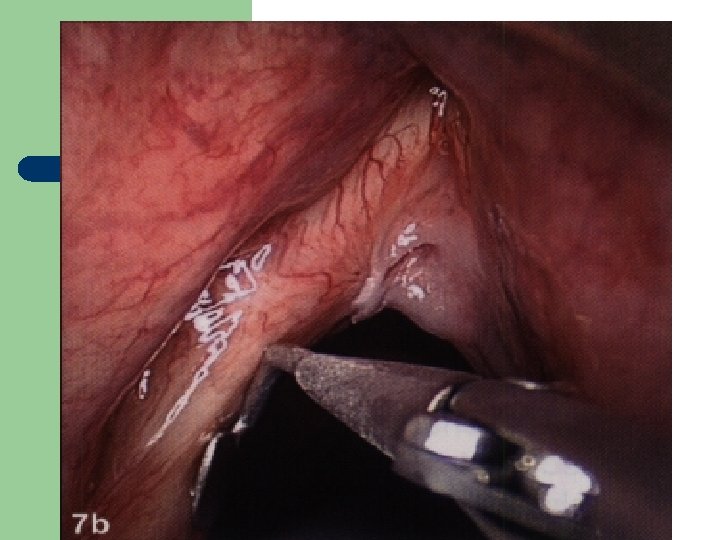

Hlasivkový uzlík l

Hlasivkový uzlík l

Hlasivkové uzlíky l